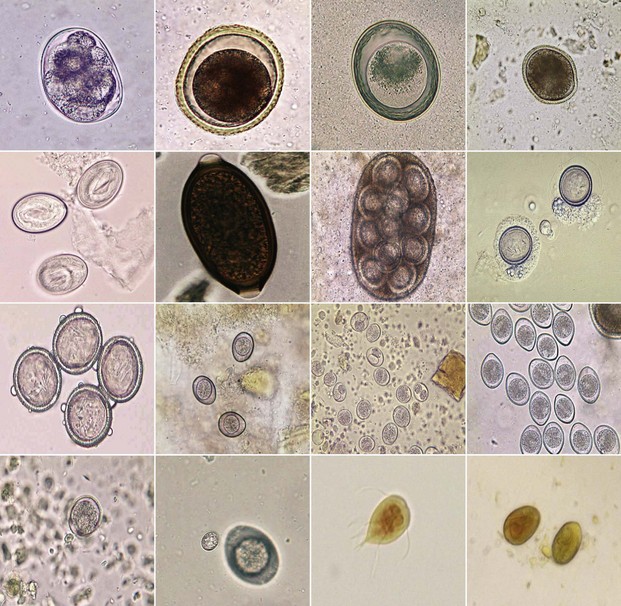

Микрофотографии яиц гельминтов Toxocara canis

Раздел: Фотоэссе